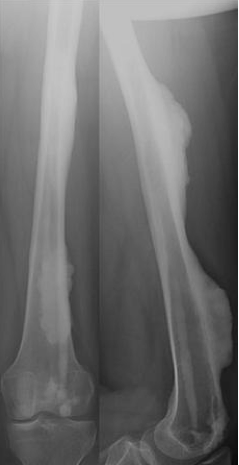

Diagnosis?

Melorheostosis

Periosteal formation of new bone

Looks like dripping candle wax